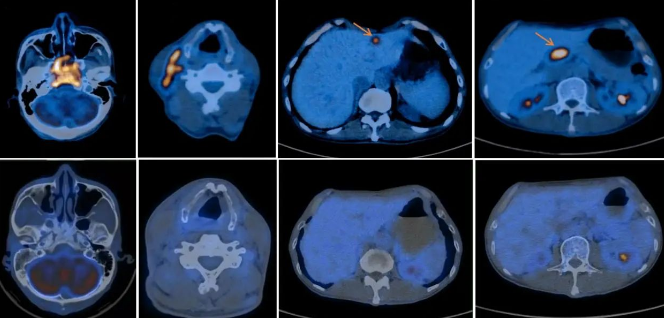

鼻咽癌伴颈部淋巴结、胰头淋巴结及肝转移治疗前后对比